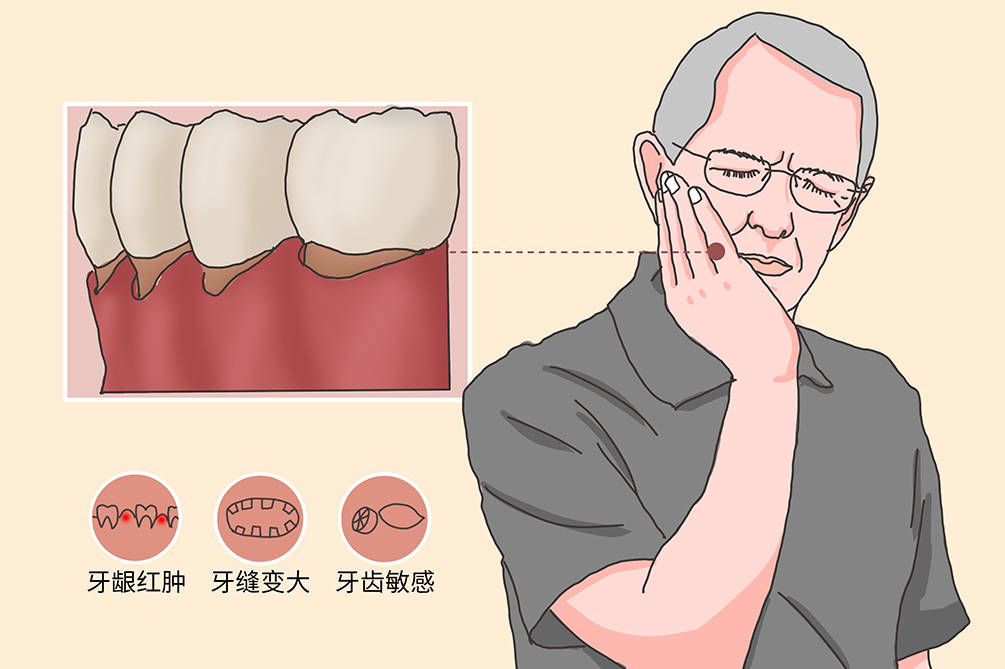

牙结石,牙龈炎,牙周炎,食物镶嵌都是刺激致使牙龈萎缩的原因。

然后牙槽周围病变,牙槽骨吸收后,附着在牙槽骨上的牙龈就会松动,出现牙龈萎缩。

牙周炎引起的牙龈萎缩在获得专业治疗之后能得到控制,但已经被破坏的牙龈组织和已经出现的牙龈萎缩是不可逆的。

但即使牙龈萎缩无法恢复,治疗也需要及时进行,只有控制病情发展,才能防止牙龈继续萎缩,避免牙齿松动甚至脱落的悲剧。

牙龈萎缩导致牙齿松动,最终导致患牙脱落。